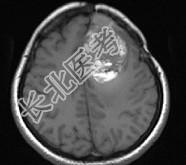

- 单项选择题女,39岁, 三年前因左额部胶质瘤手术治疗,最近出现头痛, 并抽搐大发作1次,请根据所提供图像, 选择最可能的诊断是 ( )

A、(左额叶)放射性脑炎

B、(左额叶)脑脓肿

C、(左额叶)脑出血

D、(左额叶)脑转移瘤

E、(左额叶)星形细胞瘤Ⅱ~Ⅲ级